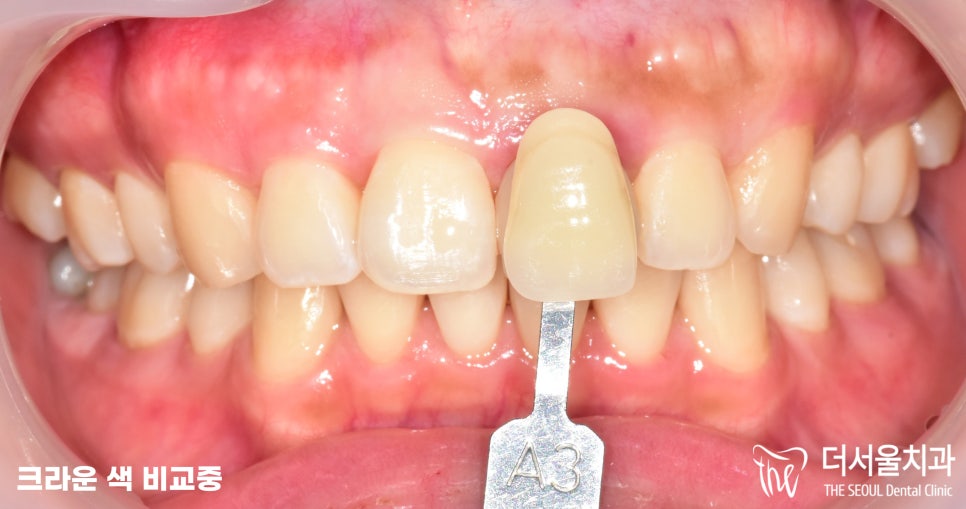

그 다음에 양 옆에 치아와

비슷한 색감의 크라운을

세팅할 수 있도록

보철을 가져다대어 비교를 해봅니다.

태평동치과 에선 A2, A3를 비교했을 때,

A2가 좀 더 적합하다 판단되어

해당 보철로 제작 후 세팅해드리기로 했습니다.

환자분 역시 A2가 더 낫다며

이것으로 하는게 좋겠다는 의견을 주셨습니다.

(카메라 플래쉬 때문에 조금 차이가 날 수 있으나,

실제로 보았을 때, 동일하게 맞춰드렸습니다.)